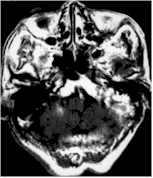

| ・CyberKnife U |

Main targeted disease

・Metastatic brain tumor

・Acoustic neuroma

・Arteriovenouse malformation

・Pituitary adenoma

・Head and neck tumor |

| Before |

After 3 months |

After 28 months |

| Cavernous hemangioma |